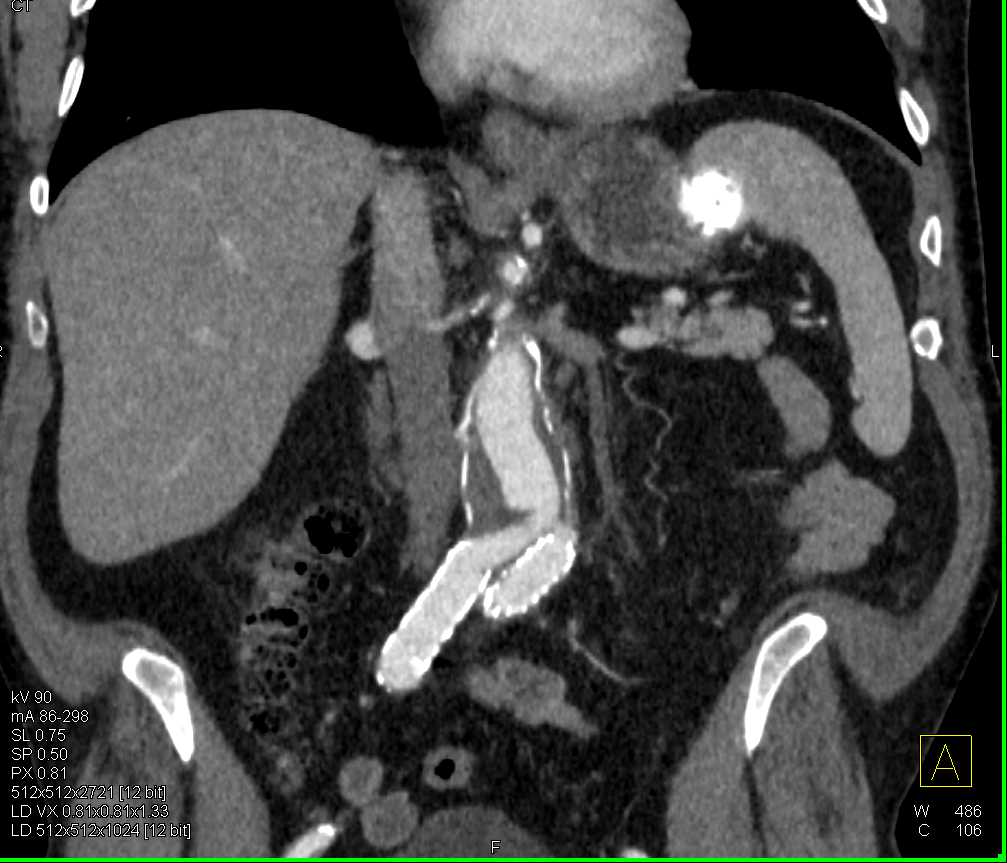

Splenic Cyst from Old Trauma